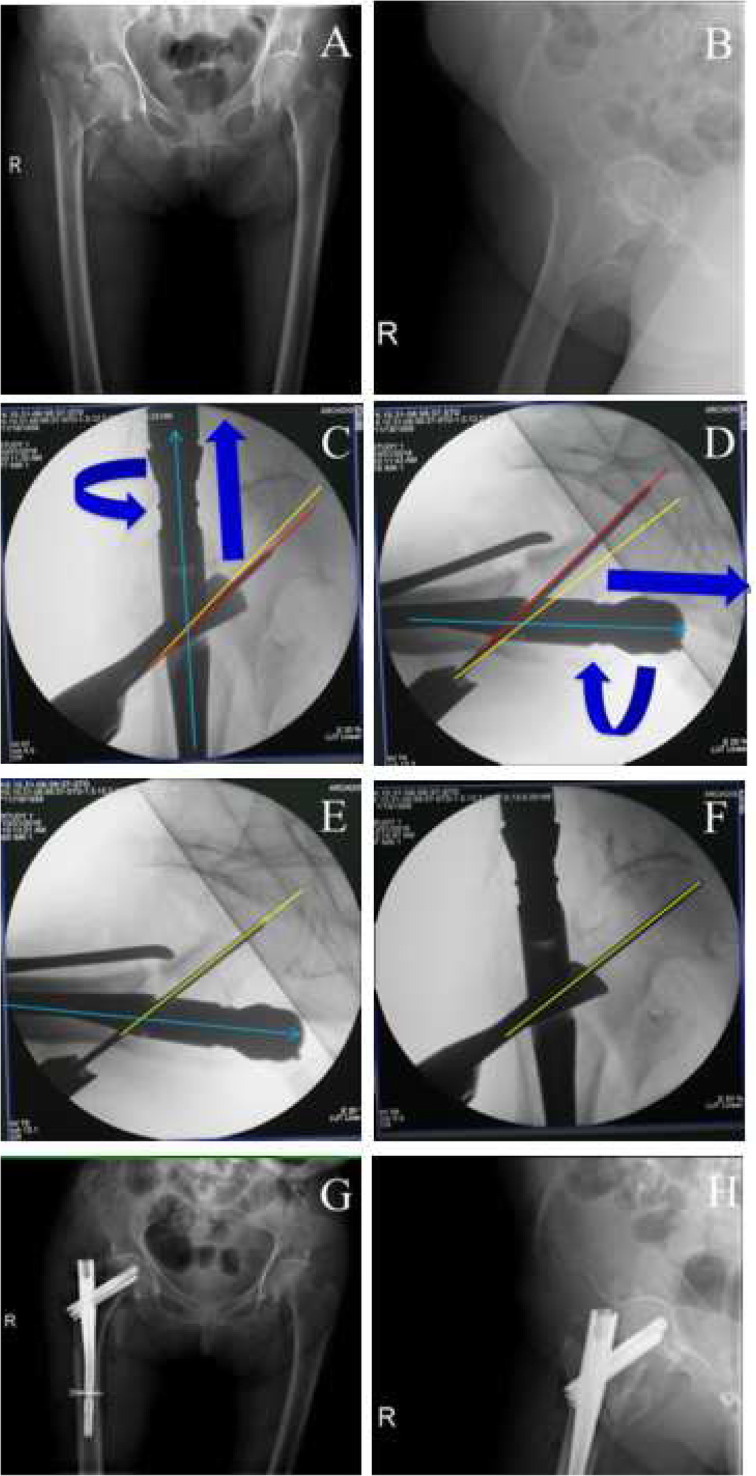

Fig. 3.

A typical case to regulate the PSA and anteversion angle to obtain ideal TAD. a-b, preoperative anteroposterior (a) and lateral (b) X-ray to diagnose intertaochanteric fractures; c-f, the adjustment of the guide pin. When position of neck guide pin is higher (the PSA is larger, c) and anteversion angle of nail is more than normal (d), we need to internally rotate the nail to make anteversion angle smaller (f) (at the same time, the PSA will become less in AP view, e) to get better TAD; g-h, postoperative anteroposterior (g) and lateral (h) X-ray to confirm the fracture reduction. Green line, nail position; red line, current position; yellow, ideal position